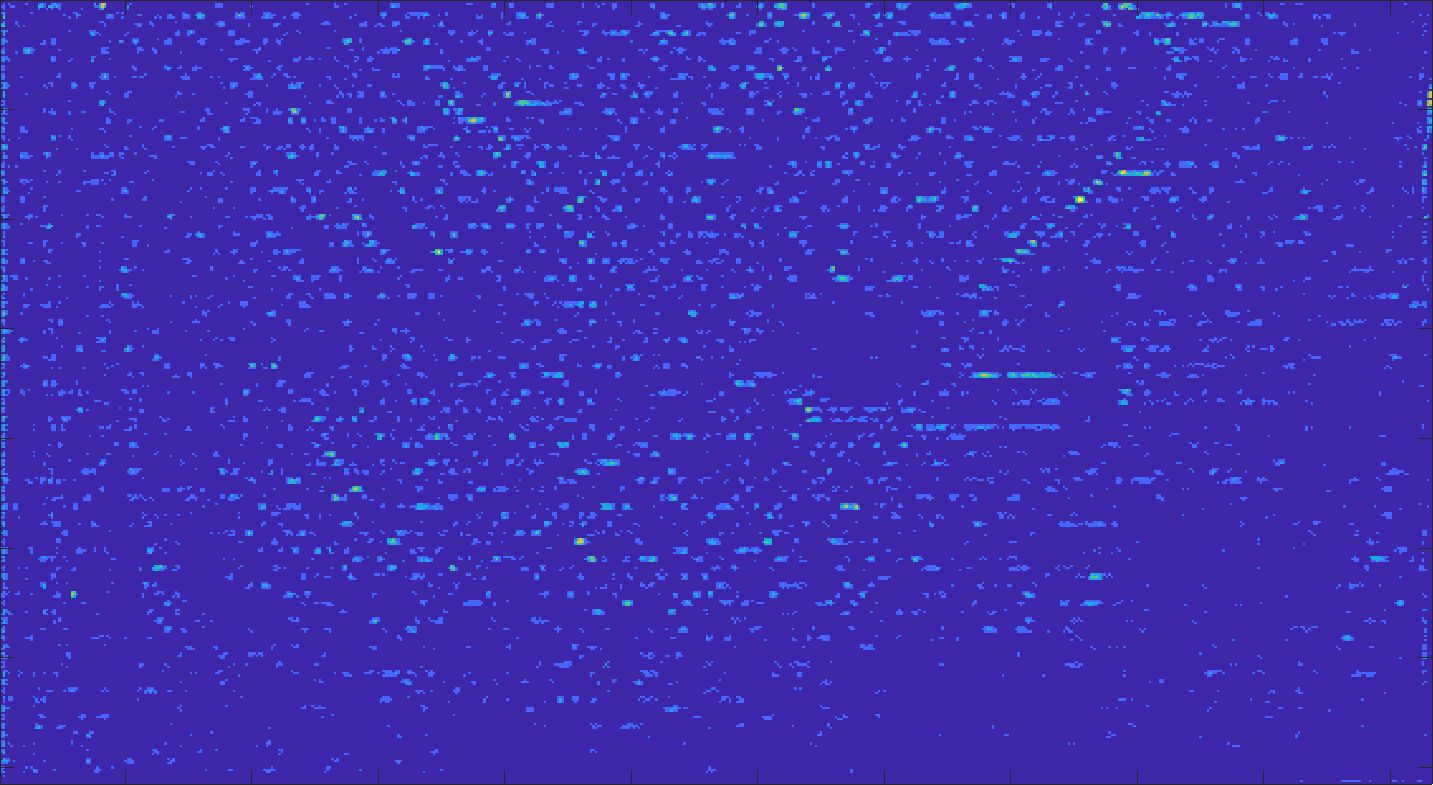

We train each learning-based network (custom-WDSR) with 1.5K images, where the input is the outcome of the selected up-sampling method (i.e., Cubic convolution), and the target is the original high-resolution image. Indeed, input and target images have the same resolution, as the reconstruction of the missing lines has been already performed by Cubic convolution. Figs. 3, 4, and 5 show the results of the network prediction, compared with the input and the target images. Target images correspond to spatial high-resolution images; input images are the outcome of the up-sampling interpolation, which is applied to spatial low-resolution images (i.e., the down-sampling along the lateral direction of high-resolution images); prediction images represent the output of the neural network.

Our framework visually improves the results, in terms of blurring and artefacts. This result is more evident in the magnification of the ear of the foetus (Fig. 3), the mitral valve (Fig. 4), and the mass edges (Fig. 5). Fig. 6 shows the error image of the three anatomical districts with both 2X and 4X up-sampling factors, with the maximum error in the scale . The error is more evident in the contours of the anatomical structures; moreover, the abdominal district shows a smaller error than the cardiac and obstetric ones. We underline that the view for each image is scaled to its maximum, to improve the visualisation of the error.

Fig. 15 shows the results of the prediction of the network, compared with the input and the target denoised images of the obstetric district. Our framework visually improves the results, in terms of blurring and artefacts. Fig. 16 shows the error image of our prediction with respect to the target denoised image, for both 2X and 4X up-sampling. The error is mainly distributed on the edges of the anatomical structure. Furthermore, the maximum error of the 2X up-sampling is 6 in the range of , showing us that our method accurately predicts the target if soft denoising is applied before up-sampling.

Fig. 17 (left) shows the box plot of the quantitative metrics, comparing the target images with the prediction and the Cubic convolution, respectively. The PSNR metric is computed on a data set of 200 images, belonging to the same district, and with the same up-sampling factor. Analysing the obstetric anatomical district and concerning the corresponding raw images (Fig. 7 (a, left)), the denoising allows the network to significantly improve the results of the up-sampling and the prediction. In particular, comparing the target images with the predicted images, the median PSNR value of obstetric 2X denoised images is 51.8, compared to the median PSNR value of obstetric 2X raw images which is 36.9.

Fig. 17 (right) shows the histogram of the absolute value of the error with respect to the target, of the prediction and Cubic convolution respectively. This result shows that our framework increase of and (2X and 4X, respectively) the number of pixels where the prediction error is lower than 5, which is very similar to the target when visually analysing the images, and improved with respect to the learning framework applied to raw images. According to Fig. 18, our method improves the accuracy of Cubic convolution. For example, the SSIM increases of on cardiac 2X and the MAE increases of on abdominal 4X.